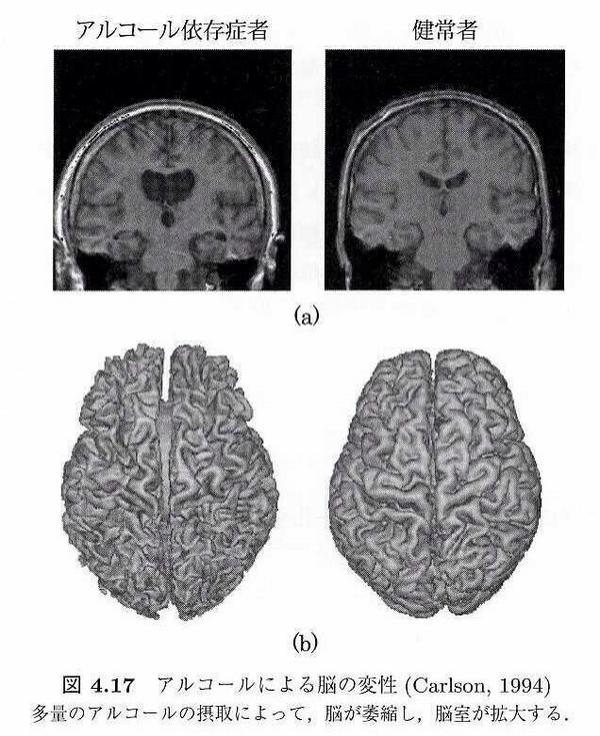

過度な飲酒 脳萎縮 招く 認知症の原因にも 脳ドック検診で確認を 日経bizgate

Med Cannabis Auf Twitter アルコールは脳を萎縮させることが知られています 対して大麻使用者の脳へのダメージは最新のmri解析をもってしても確認できていません 日本におけるアルコール依存症患者は600万人とも言われています 廃人になるのは大麻か酒か Http T